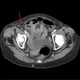

Inguinal or femoral hernia

Femoral hernias occur just below the inguinal ligament, when abdominal contents pass through a naturally occurring weakness in the abdominal wall called the femoral canal. Femoral hernias are a relatively uncommon type, accounting for only 3% of all hernias. [Source: Wikipedia ]